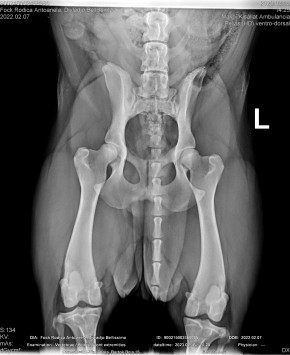

DIVLADJO BELLISSIMA

( BELLISSIMA )

Data nasterii:

07.02.2022